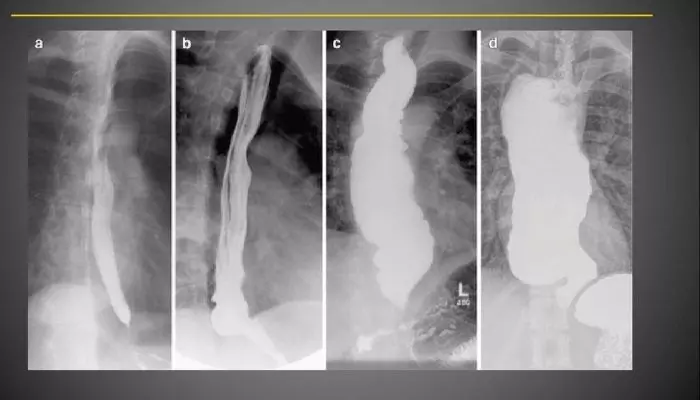

Диагностика

Как определить наличие гастроптоза? Ведь клинические проявления патологии можно спутать с другими болезнями ЖКТ. Увидеть признаки опущения желудка на поздних стадиях специалист может даже при внешнем осмотре. Признаком является отвислый живот, который при принятии пациентом горизонтального положения западает.

При поздней стадии связки растянуты настолько сильно, что они начинают раздражать нервные окончания, что провоцирует болевой синдром. Боль, как правило, возникает при движении и стихает в положении лежа. При пальпации можно обнаружить, что желудок расположен ниже своего анатомического места.

Более полную картину можно получить при использовании рентгенографии и проведении УЗИ. Эти исследования позволяют увидеть точное расположение желудка относительно других органов. Дополнительно пациент может быть направлен на проведение гастроскопии, так как гастроптоз нередко сопровождается нарушением секреции.